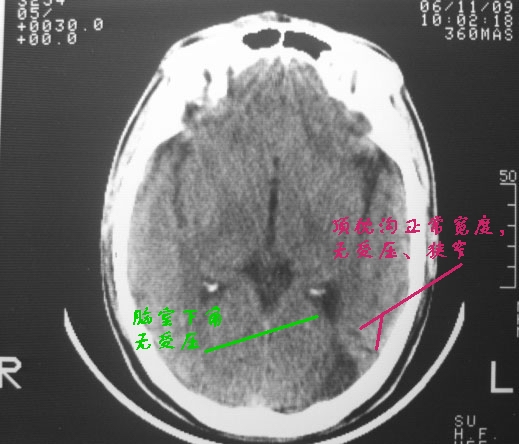

以下是引用dyqct在2006-11-9 15:04:00的发言:[br]左枕叶、双顶叶各见一处似三角形低密度区,边界尚清楚,无占位效应,累及皮质,白质侧未见灰质影。余所见未见异常。[br]考虑:1、脑软化灶;[br] 2、不支持脑裂畸形,该病病变区两侧应有灰质带——即灰质异位,临床上常有顽固性颠痫。当然了脑软化灶也偶会出现颠痫。

以下是引用守望可可西里在2006-11-9 15:06:00的发言:[br][br] 1.左侧枕叶低密度与侧脑室相通,考虑开唇型脑裂畸形。[br] 2.双侧顶叶低密度考虑局部脑沟异常扩大,发育问题。